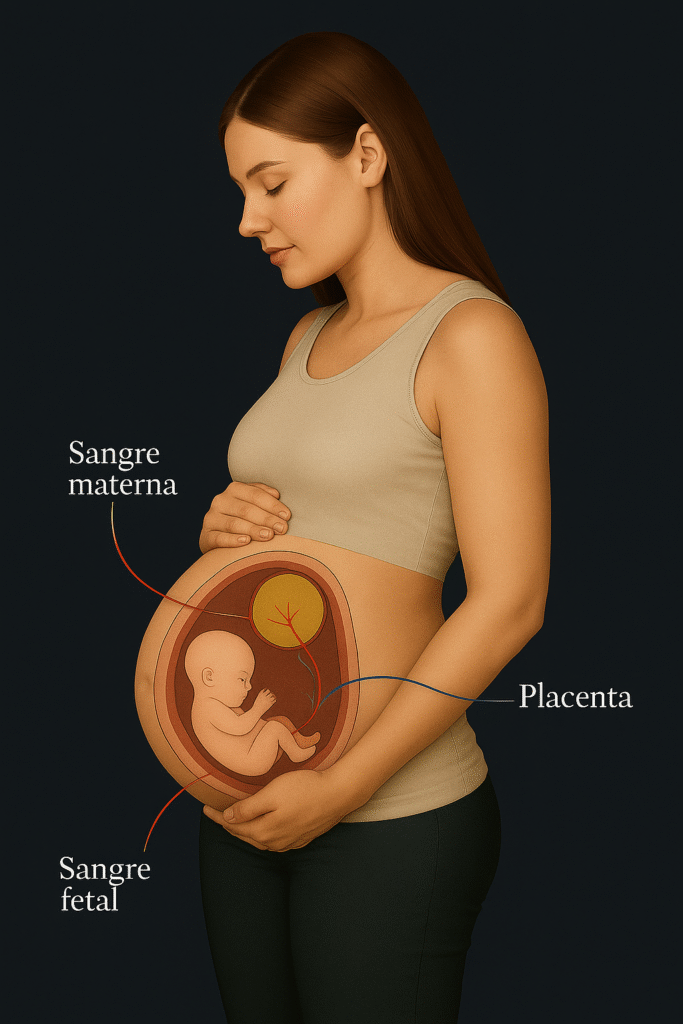

Durante el embarazo, la placenta es el puente de vida…

Durante la gestación, la placenta permite que el oxígeno y los nutrientes lleguen al bebé.

Cuando existen alteraciones genéticas o de coagulación, este flujo puede verse afectado, aumentando el riesgo de complicaciones.

Identificar a tiempo estas condiciones ofrece la oportunidad de prevenir y actuar junto con tu ginecólogo.